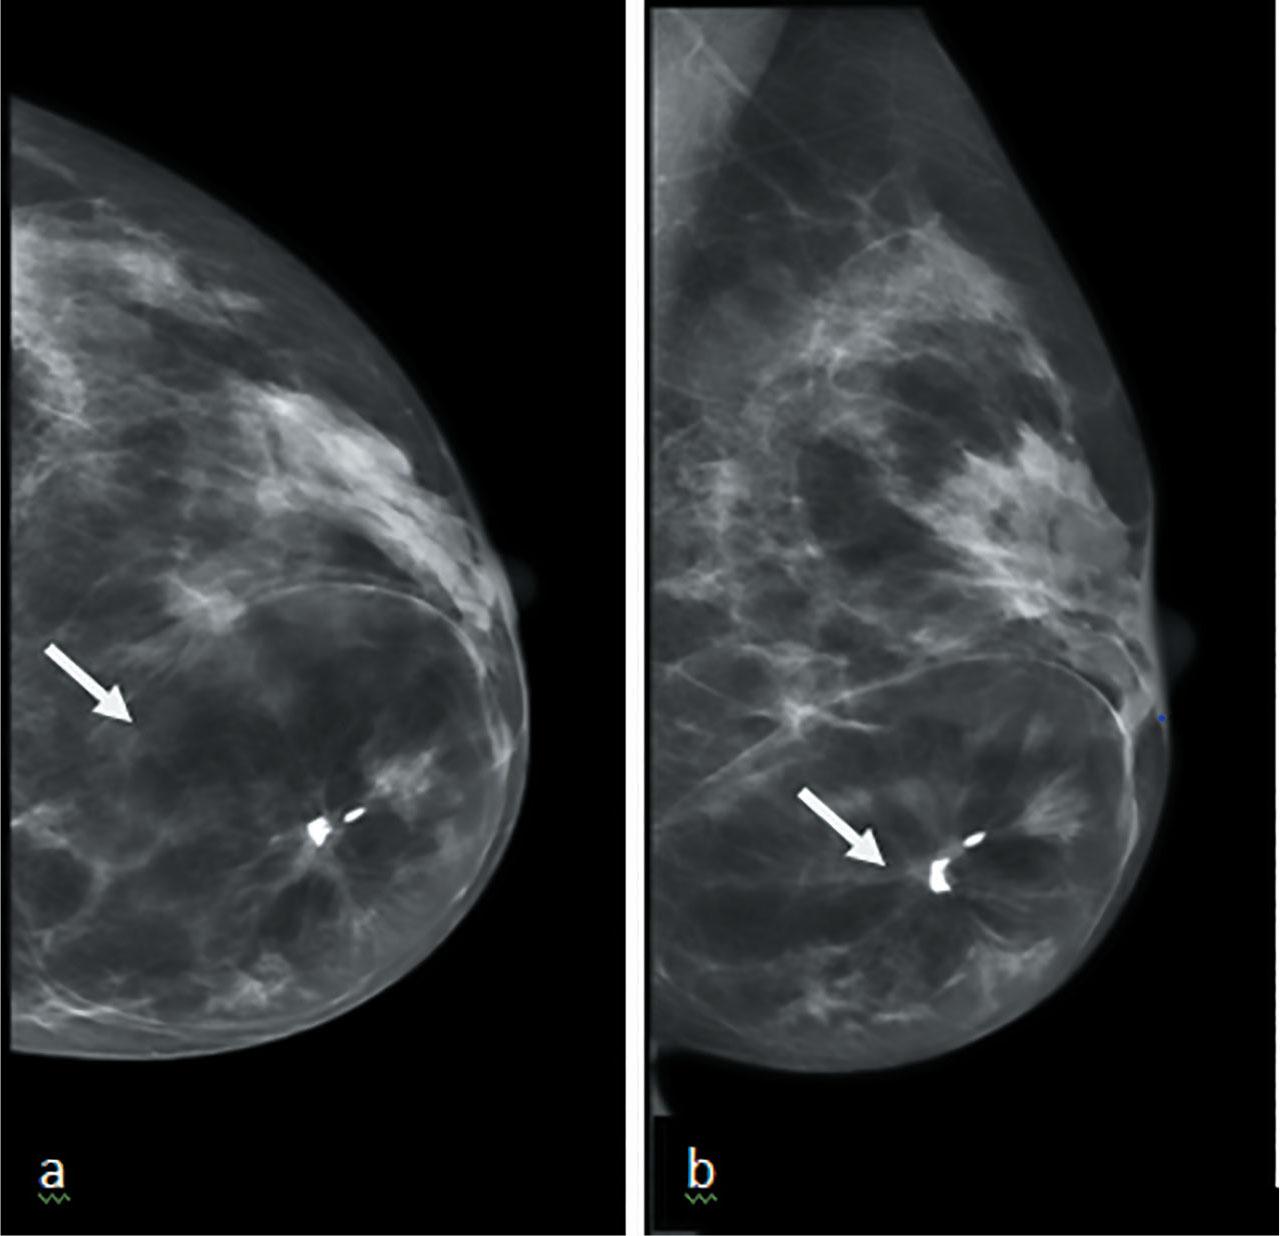

51-year-old female presented to a symptomatic breast clinic with a long standing lump in her left breast. Clinical examination of left breast showed a soft mobile mass. Examination of axilla was normal. Full field digital mammography (FFDM) and ultrasound (US) of left breast was performed. Mammography showed well encapsulated 70mm heterogenous mass consistent with a breast hamartoma in the lower inner left breast with lucent and dense areas mimicking breast tissue. The center of the hamartoma showed an area of distortion with associated calcification (Figure 1a&b). On US there was an oval, well defined heterogenous mass with posterior acoustic shadowing area (Figure 2a&b). Imaging raised suspicion of underlying malignancy within the hamartoma, and a 14 G ultrasound guided core biopsy was performed through the distortion and biopsy marker placed.

(a) CC and (b) MLO views of hamartoma, seen as encapsulated heterogenous mass in the lower and inner breast with central macrocalifications and distortion (arrows).